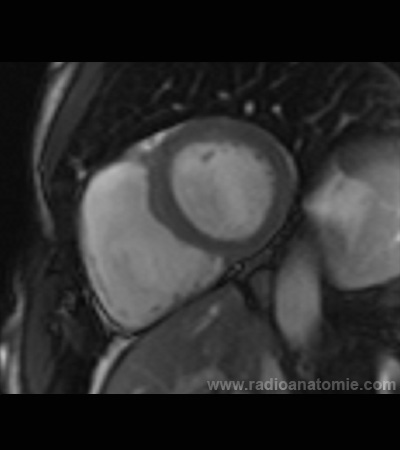

Radioanatomie et plans de coupe en IRM cardiaque

Coupe petit axe

Plan 4 cavités

Plan 2 cavités

Plan chambre de chasse du ventricule gauche (LVOT)